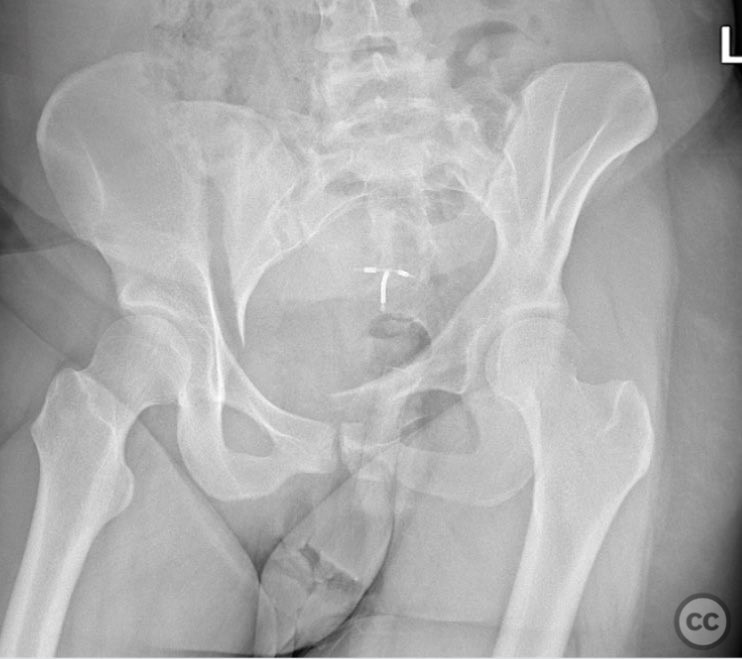

Pelvic Ring - AO/OTA 61x

Pelvis - AO/OTA 6x